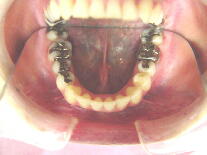

症例2 (20代 女性) 非抜歯例 ![]() ![]() ![]()

初診時平成12年6月